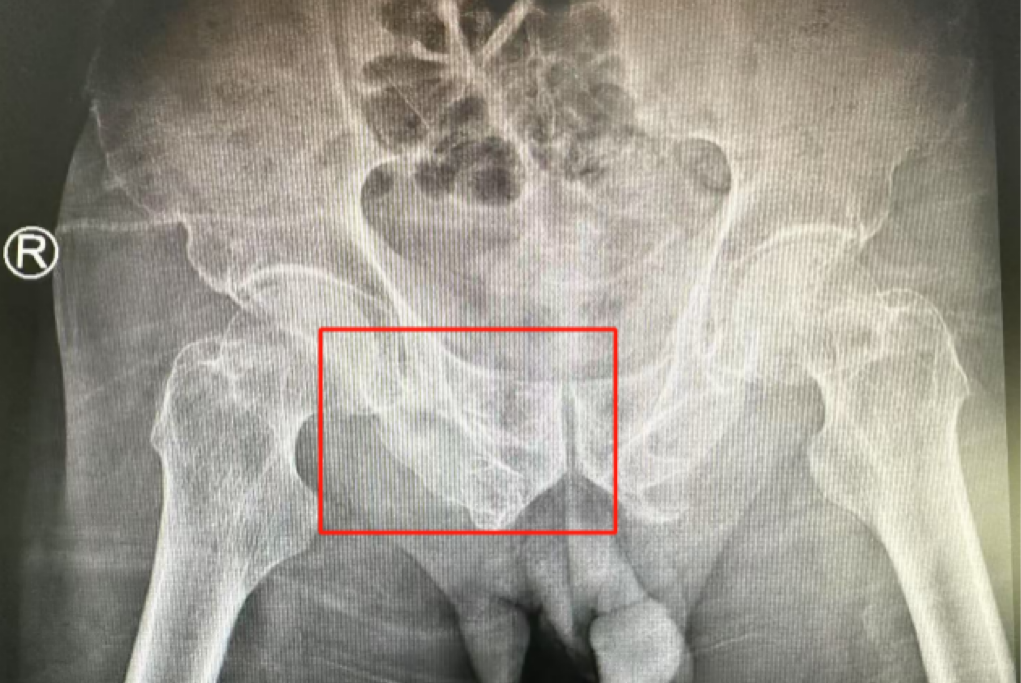

術前影像學顯示,患者的左側骶骨骨折,右側恥骨骨折、髂骨骨折,骨盆骨折分型為C型,老年脆性骨盆骨折分型為IV型,是極度不穩定型的前環骨折和雙側后環骨折。所幸沒有明顯的骨盆出血或內臟損傷的表現。

無影燈下,智能骨科團隊將患者示蹤器,放在左側髂前上棘,使用術中三維影像設備獲取骨盆的三維圖像,掃描結果傳輸至機器人導航系統,完成螺釘置入的位置和走形,并在機器人的引導下分別置入4枚通道螺釘。置入后再次進行CT掃描驗證,證實導針精確置入。

在骨科手術機器人毫米級精度的引導下,這項原本高難度、高風險的手術變得更加精準高效。手術共計耗時1個半小時,術中出血不到20毫升,每枚螺釘置入位置的切口長度約1.5厘米,完美達到了預期。術后,王大爺安全返回病房。

術后第二天,醫生團隊復查X片顯示螺釘植入位置非常滿意,骨折基本達到穩定復位,同時,復查的全血細胞計數中,血紅蛋白指數為102g/L。術后第三天,在智能骨科病房護理團隊及康復師的指導和護理下,王大爺可以坐立在床上。術后第四天,王大爺迎來了出院日,“得虧有了這么先進的醫療技術,讓我還能下地行走,謝謝你們!”

螺釘植入位置非常滿意